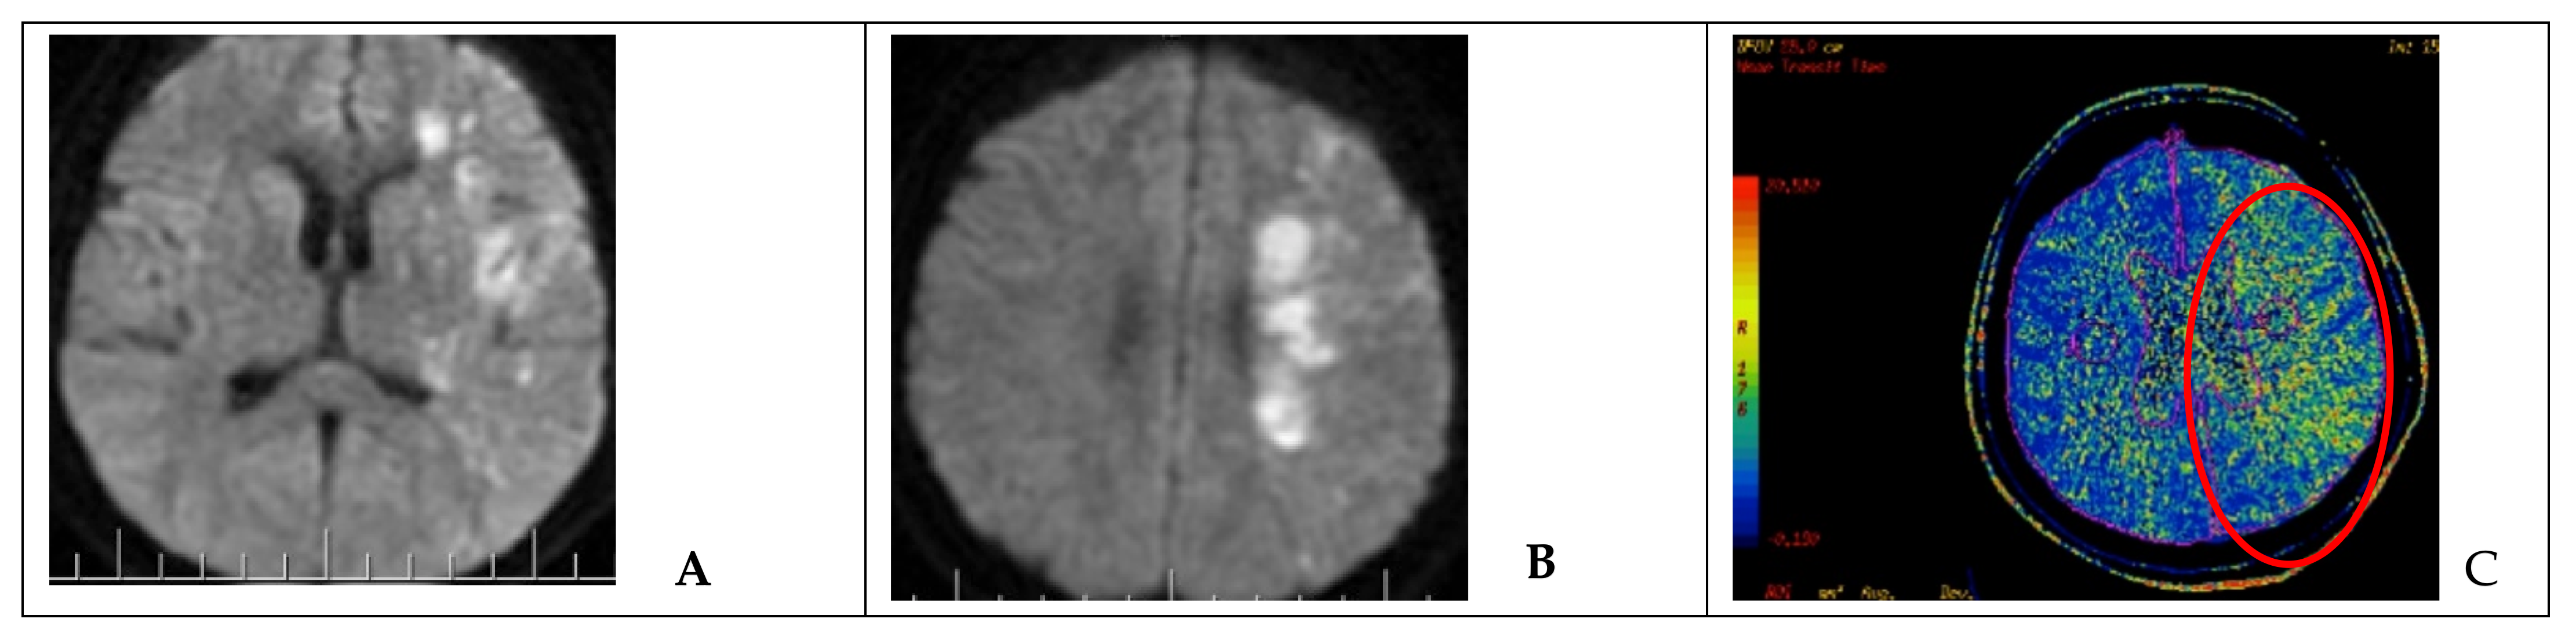

Hemiparesis occurred in one case with sufficient collateral circulation after occlusion of the injured ICA. After endovascular intervention, DWI MRI and MSCT-perfusion images showed a decrease in the cerebral blood flow and ischemic zone in the middle cerebral artery (MCA) territory on the side of the occluded ICA (Figure 3). Therefore, the patient underwent single-barrel extra-intracranial anastomosis between the superficial temporal artery and the middle cerebral artery on the left side.

Figure 3. Neuroimaging in a patient after endovascular occlusion of the ICA (clinical case 5). (A,B) MRI of the brain (DWI); an area of acute ischemic injury in the left hemisphere (hyperintense area) can be visualized. (C) MSCT-perfusion study demonstrating signs of cerebral circulation insufficiency in the form of prolonged blood transit time in the basin of the left MCA (red circled area).